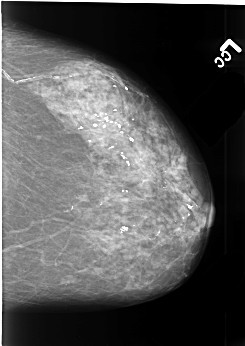

B_3411_1.LEFT_MLO

LEFT_MLO LINES 4464 PIXELS_PER_LINE 3344 BITS_PER_PIXEL 12 RESOLUTION 50 NON_OVERLAY